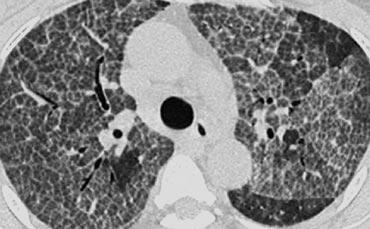

Ca lâm sàng minh họa: Protein phế nang

Hình ảnh: Bệnh nhân có dày vách liên tiểu thùy kết hợp mờ kính mờ dạng đốm. Một số tiểu thùy bị tổn thương trong khi các tiểu thùy khác được bảo tồn.

Sự kết hợp này được gọi là “crazy-paving” (dạng lát đá không đều).

Dấu hiệu Crazy-Paving:

- Ban đầu được coi là đặc hiệu cho protein phế nang, nhưng hiện nay được ghi nhận trong nhiều bệnh lý, bao gồm:

- Viêm phổi do Pneumocystis jirovecii

- Ung thư biểu mô phế quản-phế nang

- Sarcoidosis

- Viêm phổi kẽ không đặc hiệu (NSIP)

- Viêm phổi tổ chức hóa (COP)

- Hội chứng suy hô hấp cấp tính ở người lớn (ARDS)

- Xuất huyết phổi

Protein phế nang:

- Một bệnh phổi lan tỏa hiếm gặp, chưa rõ nguyên nhân.

- Đặc trưng bởi sự tích tụ trong phế nang và mô kẽ của chất phospholipo-protein dương tính với phản ứng acid periodic-Schiff (PAS), có nguồn gốc từ surfactant.